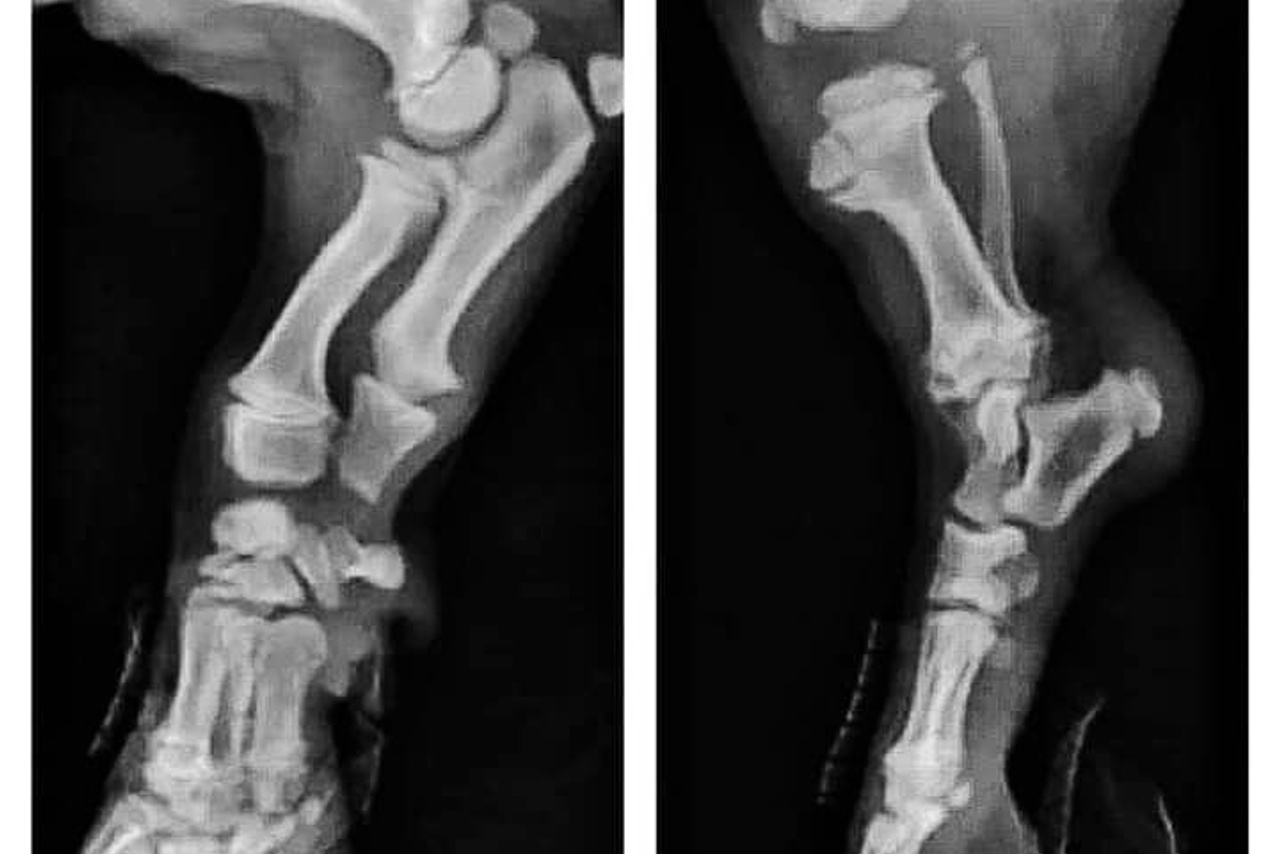

Кривое радио, также известное как лучевая кривизна, — ортопедическая аномалия, которая влияет на структуру радиокости...